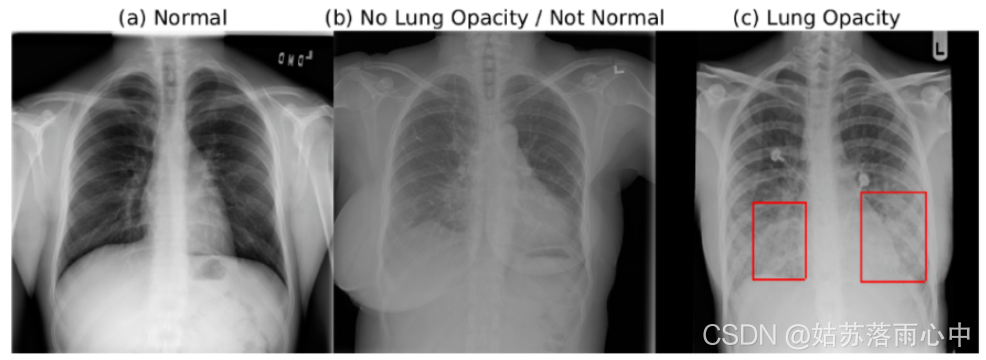

在数据集中有三类:

文章提出了一个基于单个模型的解决方案,该模型集成了多个checkpoints。该模型使用了在ImageNet 上经过预训练的SE-ResNext101作为主干网络,整体网络框架使用的是 RetinaNet SSD。

- 使用以下类别之一(“无肺不透明/不正常”,“正常”,“肺不透明”)对全局图像进行分类的额外输出添加到模型中。因此,总损失由该全局分类输出与回归损失和单个框分类损失合并而成。